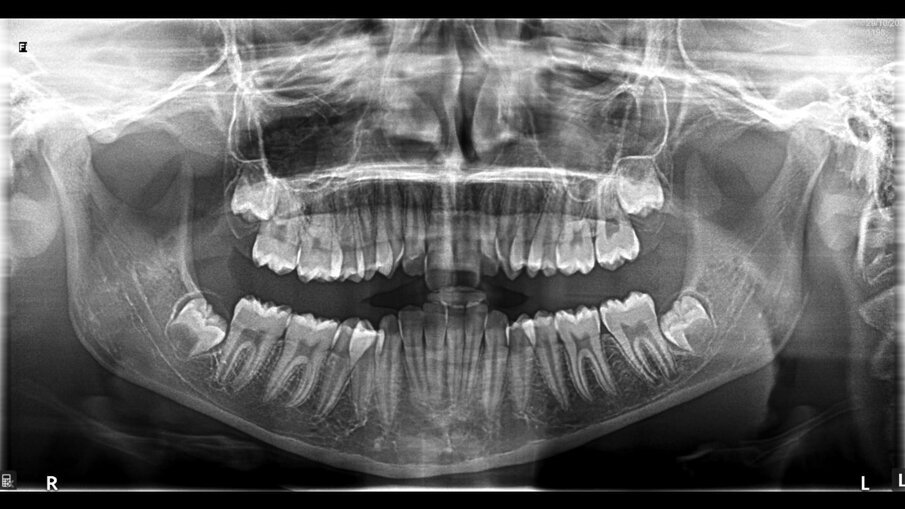

All’esame obiettivo intraorale si riscontra sul piano frontale un severo morso profondo con precontatto traumatico degli incisivi superiori contro la papilla retroincisiva e le rughe palatine anteriori durante la massima intercuspidazione, con overbite di 10 mm (Fig. 5). Dalle foto laterali si evidenzia una malocclusione di Classe II divisione 2 con scissor bite dell’elemento 1.5 (Figg. 6, 7), mentre dalle foto occlusali si rileva un grave affollamento con contrazione di entrambe le arcate maggiore nella zona premolare (Figg. 8, 9). L’analisi di Bolton mostra un eccesso superiore 3-3 di 2,34 mm (73,6%) e 6-6 di 2,76 mm (88,8%). L’analisi cefalometrica evidenzia una Classe II scheletrica, modello facciale normodivergente, angolo interincisale aumentato, incisivi superiori e inferiori retroinclinati (Fig. 10). La radiografia panoramica mostra la presenza dei germi dei terzi molari, assenza di parallelismo tra le radici dei premolari inferiori (Fig. 11) e una sovraeruzione degli incisivi inferiori che crea un doppio piano tra gli incisivi e i molari, segno di una curva di Spee molto profonda.

Fig. 11_Ortopantomografia pre-trattamento.